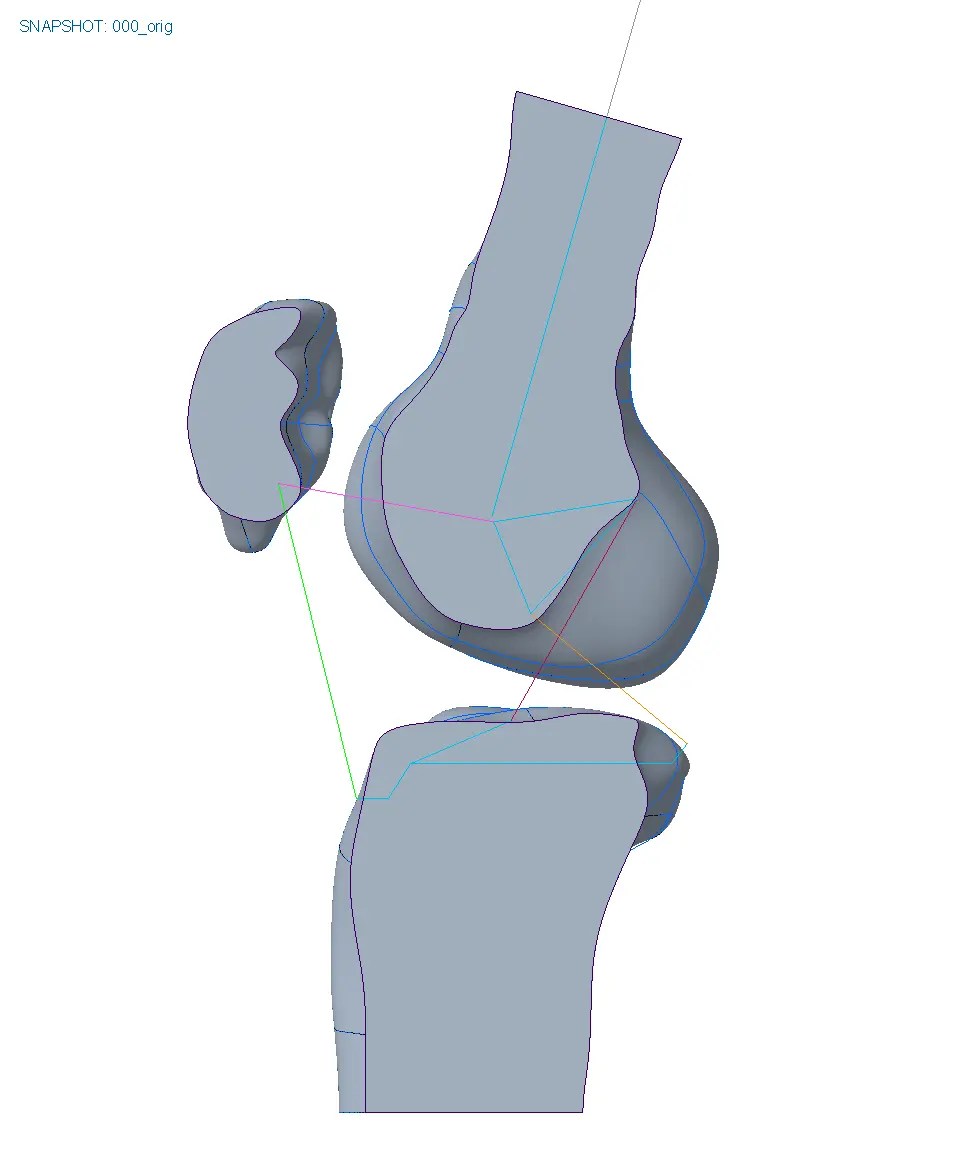

To give a more detailoed picture we built up a motion skeleton to move the bones and used the biomechanics of the knee to place the hinge and to create the design.

The motion designed brace fits like a gove and moves perfectly with the knee.

build frame

move knee

brace motion